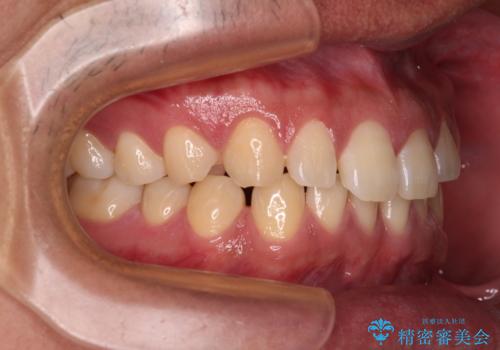

- 上下前歯の隙間を気にして来院された患者様です。

飲み込みや話をするときに舌を突出させる癖が強くあり、それが原因でスペースが空いていました。

舌癖を改善するためのトレーニングを行いながら、ワイヤー装置を用いて前歯の隙間を閉じていくこととしました。